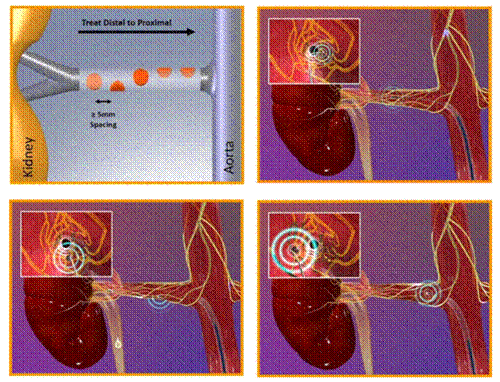

Symplicity HTN-1 (catheter-based renal sympathetic denervation for resistant hypertension: a multicentre safety and proof-of-principle cohort study) là nghiên cứu đầu tiên về tính khả thi, tính an toàn và hiệu quả trên người của phương pháp triệt phá thần kinh giao cảm động mạch thận qua đường ống thông. Nghiên cứu được thực hiện trên nhiều trung tâm tại Australia, 45 bệnh nhân tăng huyết áp kháng trị đã được triệt đốt thần kinh giao cảm động mạch thận hai bên bằng năng lượng sóng tần số radio. Quy trình kỹ thuật trong Symplicity HTN-1: Các bệnh nhân sau khi thỏa mãn các tiêu chuẩn lựa chọn của nghiên cứu sẽ được chuẩn bị cho một thủ thuật thăm dò chảy máu và được chụp động mạch thận chọn lọc qua đường động mạch đùi. Sau đó, một ống thông dẫn (guide catheter) đường kính 8 French sẽ được luồn vào lỗ vào động mạch thận, qua đó, ống thông đốt với kích thước nhỏ hơn sẽ được đưa sâu vào trong động mạch thận để tiến hành triệt đốt thần kinh giao cảm từ phía nội mạch. Ống thông đốt với đặc điểm có thể điều khiển gấp duỗi được bởi bác sĩ thủ thuật (steerable) cho phép triệt đốt thành một đường xoắn ốc vòng quanh lòng động mạch thận từng bên. Cũng tương tự như quy trình triệt đốt các rối loạn nhịp tim bằng năng lượng tần số radio, quá trình đốt mạch thận được kiểm soát bởi các thông số nhiệt độ và điện trở nhằm đảm bảo năng lượng đủ để gây tổn thương mô, cắt đứt các đường dẫn truyền thần kinh giao cảm nhưng không tăng nhiệt độ quá cao gây tổn thương nội mạc làm hẹp động mạch thận. Trong Symplicity HTN-1, có 2 biến chứng liên quan đến thủ thuật được ghi nhận: 1 trường hợp lóc tách nội mạc mạch thận do đầu ống thông đốt. Động mạch thận bị lóc tách sau đó đã được đặt Stent; 1 trường hợp giả phình động mạch đùi do chọc mạch.

Hình 3: Lược đồ kỹ thuật trong nghiên cứu Symplicity HTN 1-2

30 bệnh nhân tăng huyết áp kháng trị (với số thuốc hạ áp trung bình đang sử dụng là 6) đã được chọn vào nghiên cứu. Trước thủ thuật, các bệnh nhân được đánh giá lâm sàng toàn diện và đo huyết áp liên tục trong 24 giờ cũng như các xét nghiệm về chức năng thận. Các bệnh nhân được chụp động mạch thận kiểm tra, những trường hợp có hẹp động mạch thận > 50% sẽ không tiếp tục tiến hành thủ thuật và loại ra khỏi nghiên cứu. Ống thông đốt được đưa vào động mạch thận qua đường động mạch đùi phải, triệt đốt được thực hiện lần lượt từ bên, mỗi động mạch thận sẽ được triệt đốt 6-8 điểm dọc theo chiều dài, thời gian đốt mỗi điểm là 60 giây, cường độ năng lượng sử dụng bắt đầu rất thấp và tăng dần lên tới 8-13 W, quá trình đốt được theo dõi chặt chẽ bằng các thông số nhiệt độ và trở kháng mô. Heparin TM được sử dụng nhằm duy trì ACT từ 250 đến 300 giây. Một số bệnh nhân xuất hiện cảm giác đau bụng khi đốt điện được sử dụng các thuốc giảm đau ngay trong thủ thuật. Sau khi các điểm triệt đốt đã hoàn tất, các tác giả tiến hành chụp kiểm tra lại động mạch thận 2 bên nhằm đánh giá các tổn thương mới xuất hiện.